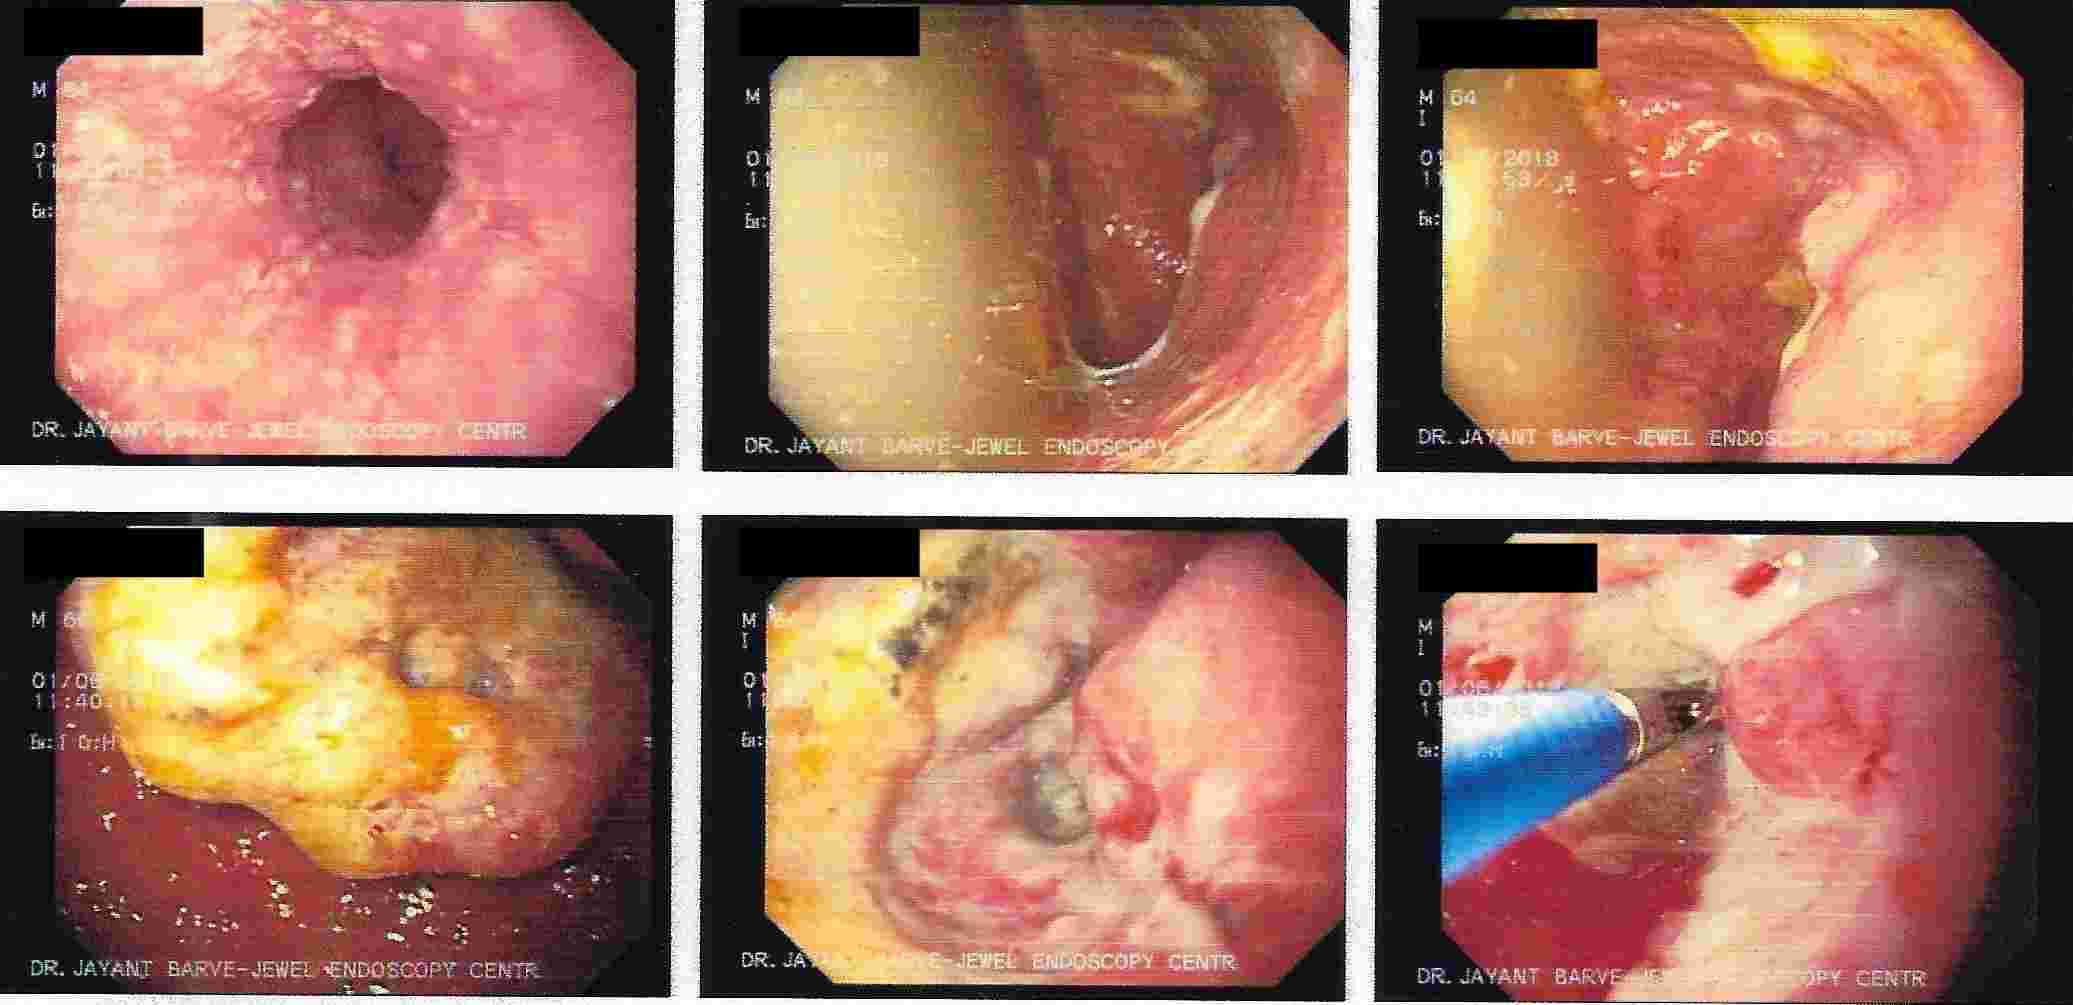

Stomach Outlet Obstruction

Causing Abdominal Fullness and Vomiting

Cancer of the Stomach with Vomiting